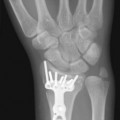

Radical debridement with elimination of all nonviable tissue is the crucial step in the management of these injuries. This is performed under tourniquet control to provide the best visualization of the extent of injury and to prevent iatrogenic injury to intact structures. Once nerves and vessels are identified, the tourniquet may be released to assess the viability of the remaining tissue better (Fig. 12.1).